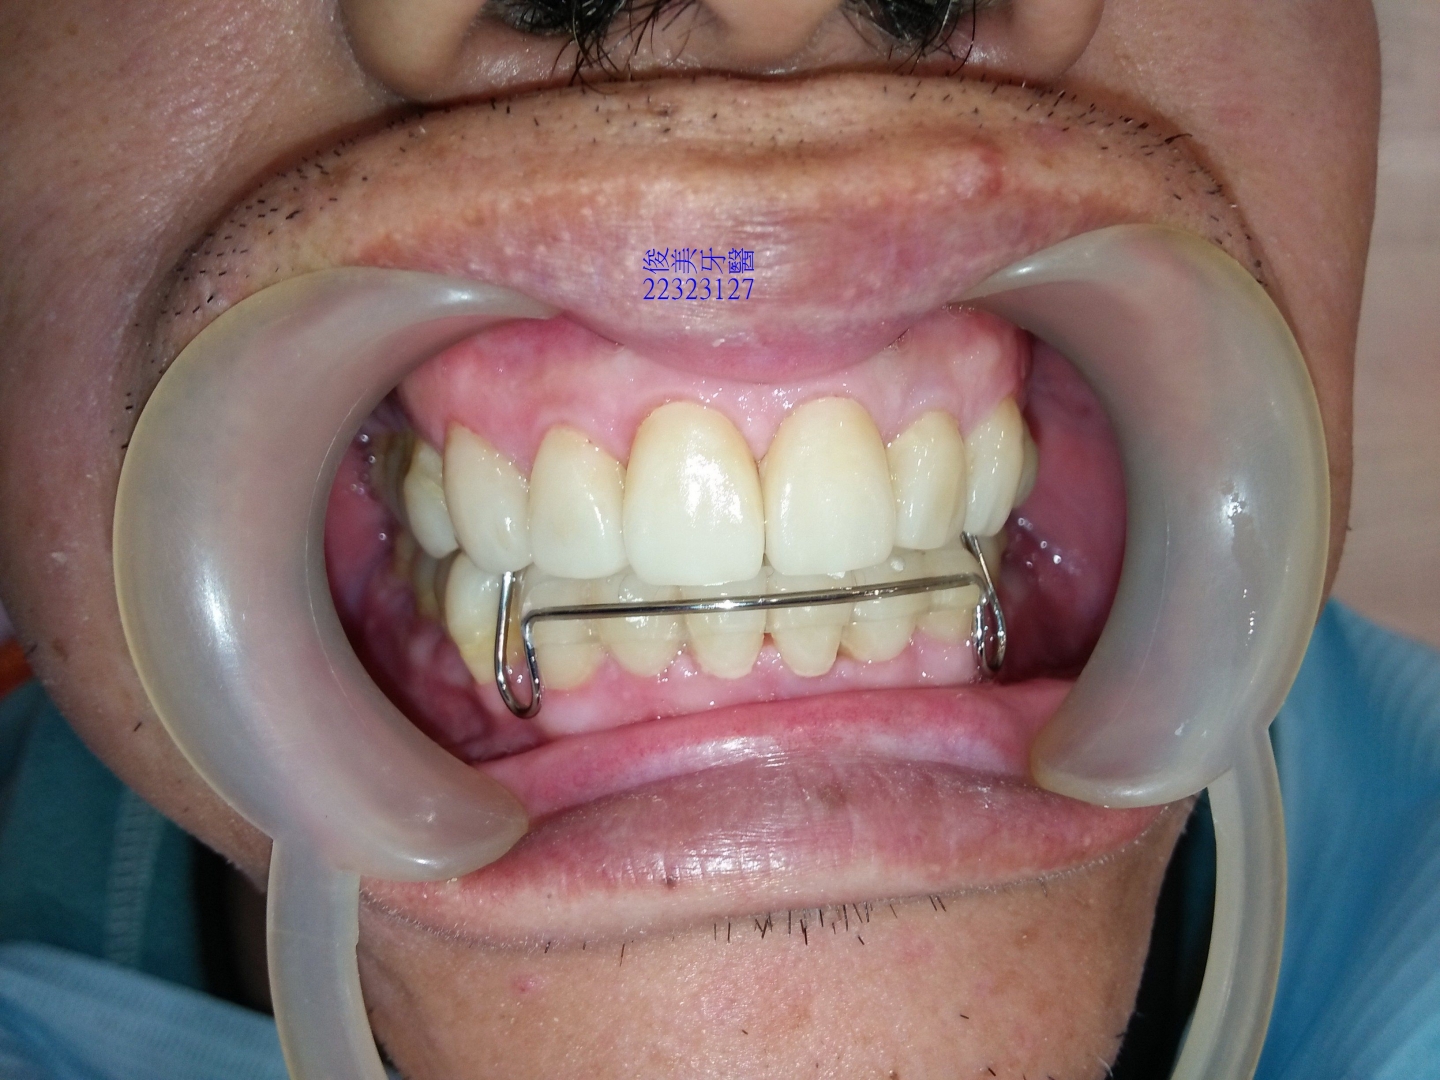

經過整合性治療......

利用矯正方式將患者的下顎牙弓擴張為原來的大小、恢復患者後牙喪失的高度,最後將前牙磨損的牙齒以

全瓷晶鑽貼片做修復,達到美觀的功能。

治療完成後,需配戴維持器。

咬合狀況。

後牙高度已建立,恢復琺瑯質的厚度。